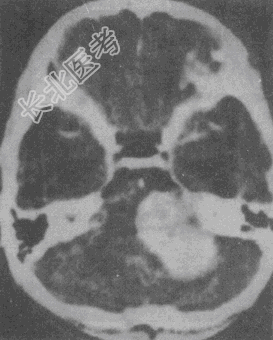

- 单项选择题女性,43岁。左侧听力下降伴左侧面部不适7个月, 根据CT图像(见图),最可能的诊断是

A、听神经瘤

B、三叉神经鞘瘤

C、脑膜瘤

D、海绵状血管瘤

E、动脉瘤